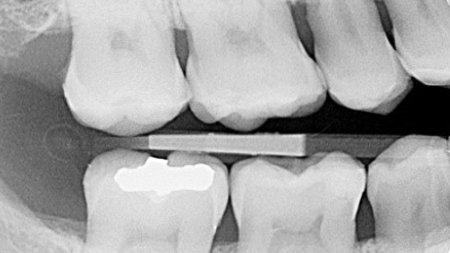

In 2010, an insufficient amalgam restoration in this first molar was replaced with condensable composite. Ten years later, it was again necessary to take action. Wear of the disto-occlusal surface resulted in dentin exposure in the composite restoration. The remaining enamel on the occlusal surface is visible. Due to sensitivity issues, the restoration was required. In addition, recurrent caries could be observed. Another contributing factor was the loss of occlusal contact caused by previous orthodontic treatment. The decision was made to reconstruct the tooth with a minimally invasive direct composite restoration.

Bitewing radiograph of the initial situation.